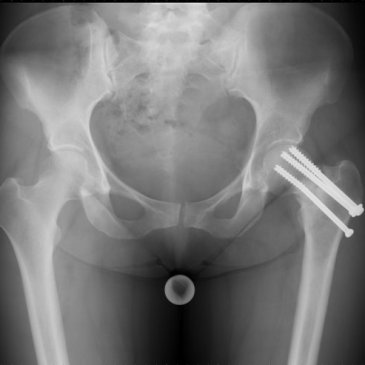

I always keep meaning to return to regular posting, but each time I mean to do anything these days my health seems to poke its proverbial tongue at me and say “Haha, not today, loser”. To be frank, I’m tired of all of it: the seizures; the panic attacks; post-menopause issues (which, it turns out, … More 2025 So Far: Musings